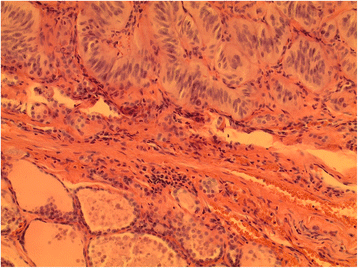

HTT (superior) juxtaposed with uninvolved thyroid parenchyma (inferior) with intervening fibrous capsule (H&E, 200X)

Fig. 2